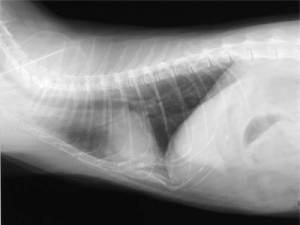

−猫ぜんそく−

○ レントゲン検査、血液検査などで総合的に診断します